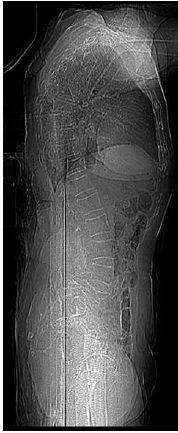

Paciente de 92 anos, de forma súbita e sem causa aparente, iniciou com dor lombar, sem irradiação, que a incomodava para caminhar, sentar e deitar. Sua radiografia de coluna lombar mostrou o seguinte:

(Arquivo pessoal; imagem usada com autorização)